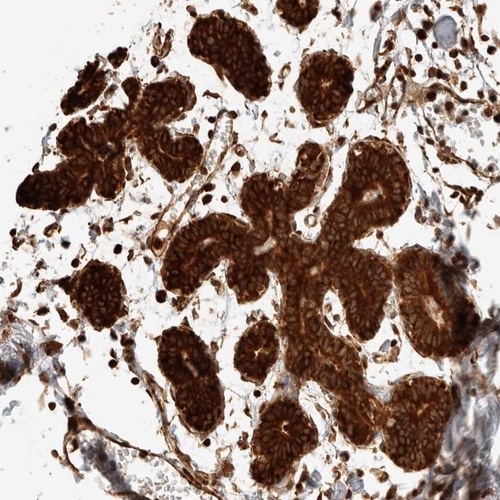

Immunohistochemical staining of human breast shows strong cytoplasmic positivity in glandular cells.